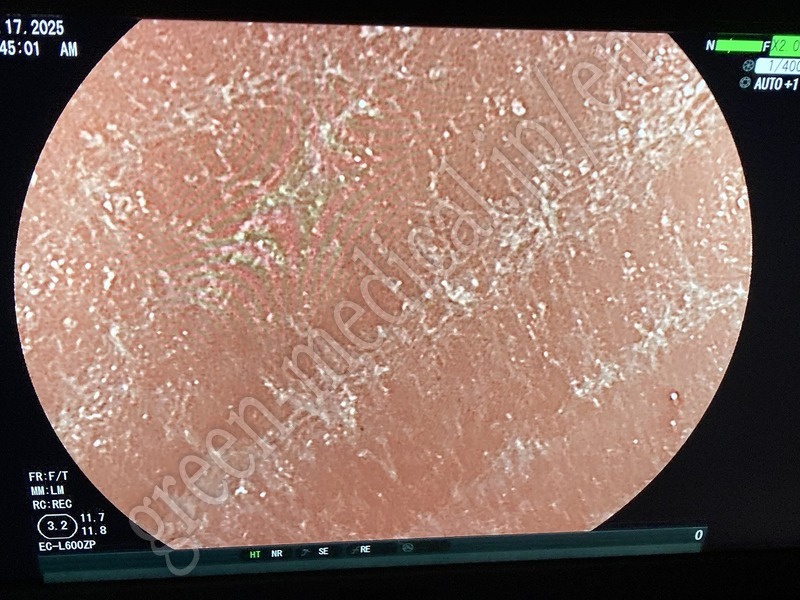

Video Colonoscope EC-L600ZP

Fabricante

FUJIFILM

Tipo

EC-L600ZP

Inventario

115327